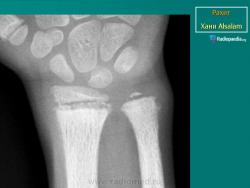

Рентгенологически начало излечения определяется по отложению солей. На участках энхондрального окостенения становится заметной новая зона препараторного обызвествления - в середине светлой рахитической зоны появляется темная, неровная, дугообразная полоска, но не на конце окостеневшего метафиза, а в суставном конце кости, обозначая, с одной стороны, остеоидное метафизарное вещество, а с другой - ростковую зону. Зона постепенно расширяется в направлении метафиза, она дает очень интенсивную гомогенную или неравномерной плотности тень. Структура восстанавливается лишь через много месяцев, она остается более плотной, на основании чего угадывается бывший процесс. При рецидивах зона препараторного обызвествления вновь разрыхляется, в результате каждая ремиссия делается заметной по чередованию светлых и темных участков, расположенных перпендикулярно к длиннику кости. Ядра окостенения также окружаются темной полосой зоны обызвествления. При рецидивах эта зона может принять слоистый характер.